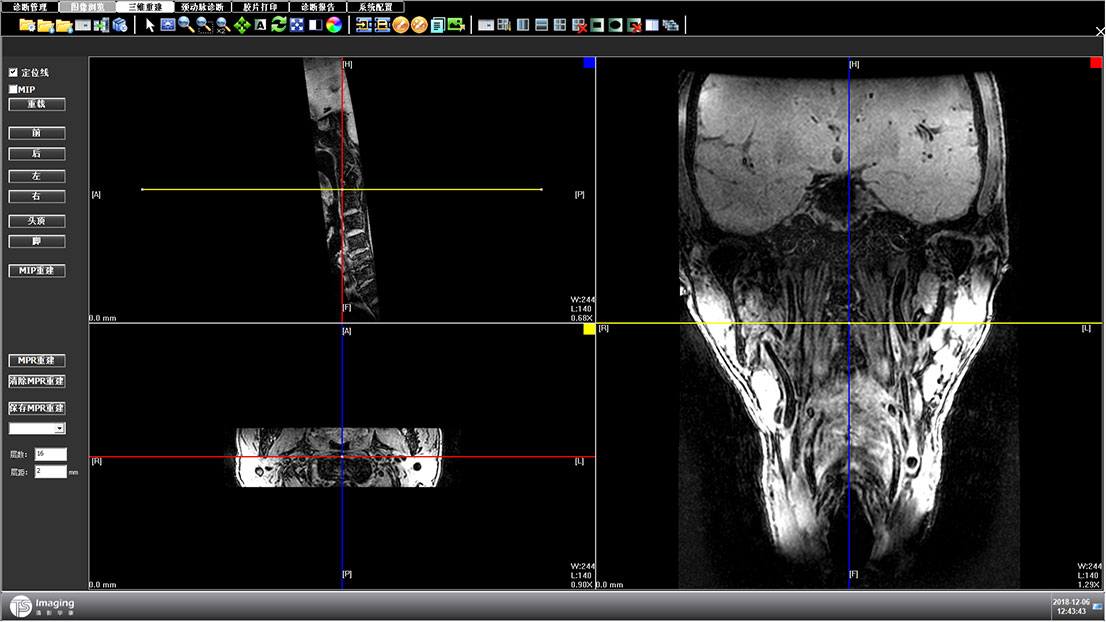

三維重建頁面

三維重建頁面從用戶的使用習慣上把操作按鈕放到了右側,進行交互上的優化,上側的操作按鈕進行統一設計和現有頁面保持風格的統一。左側的操作區域可收縮,收起來時可更好的展示圖像。